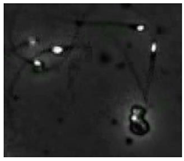

| Case | Original Frame | Detection Result |

|---|---|---|

| 1. Failure example from the validation dataset (false positive) | ![]() | ![]() |

| 2. Failure example from the test dataset (false positive) | ![]() | ![]() |

| 3. Failure example from the test dataset (false negative) | ![]() | ![]() |